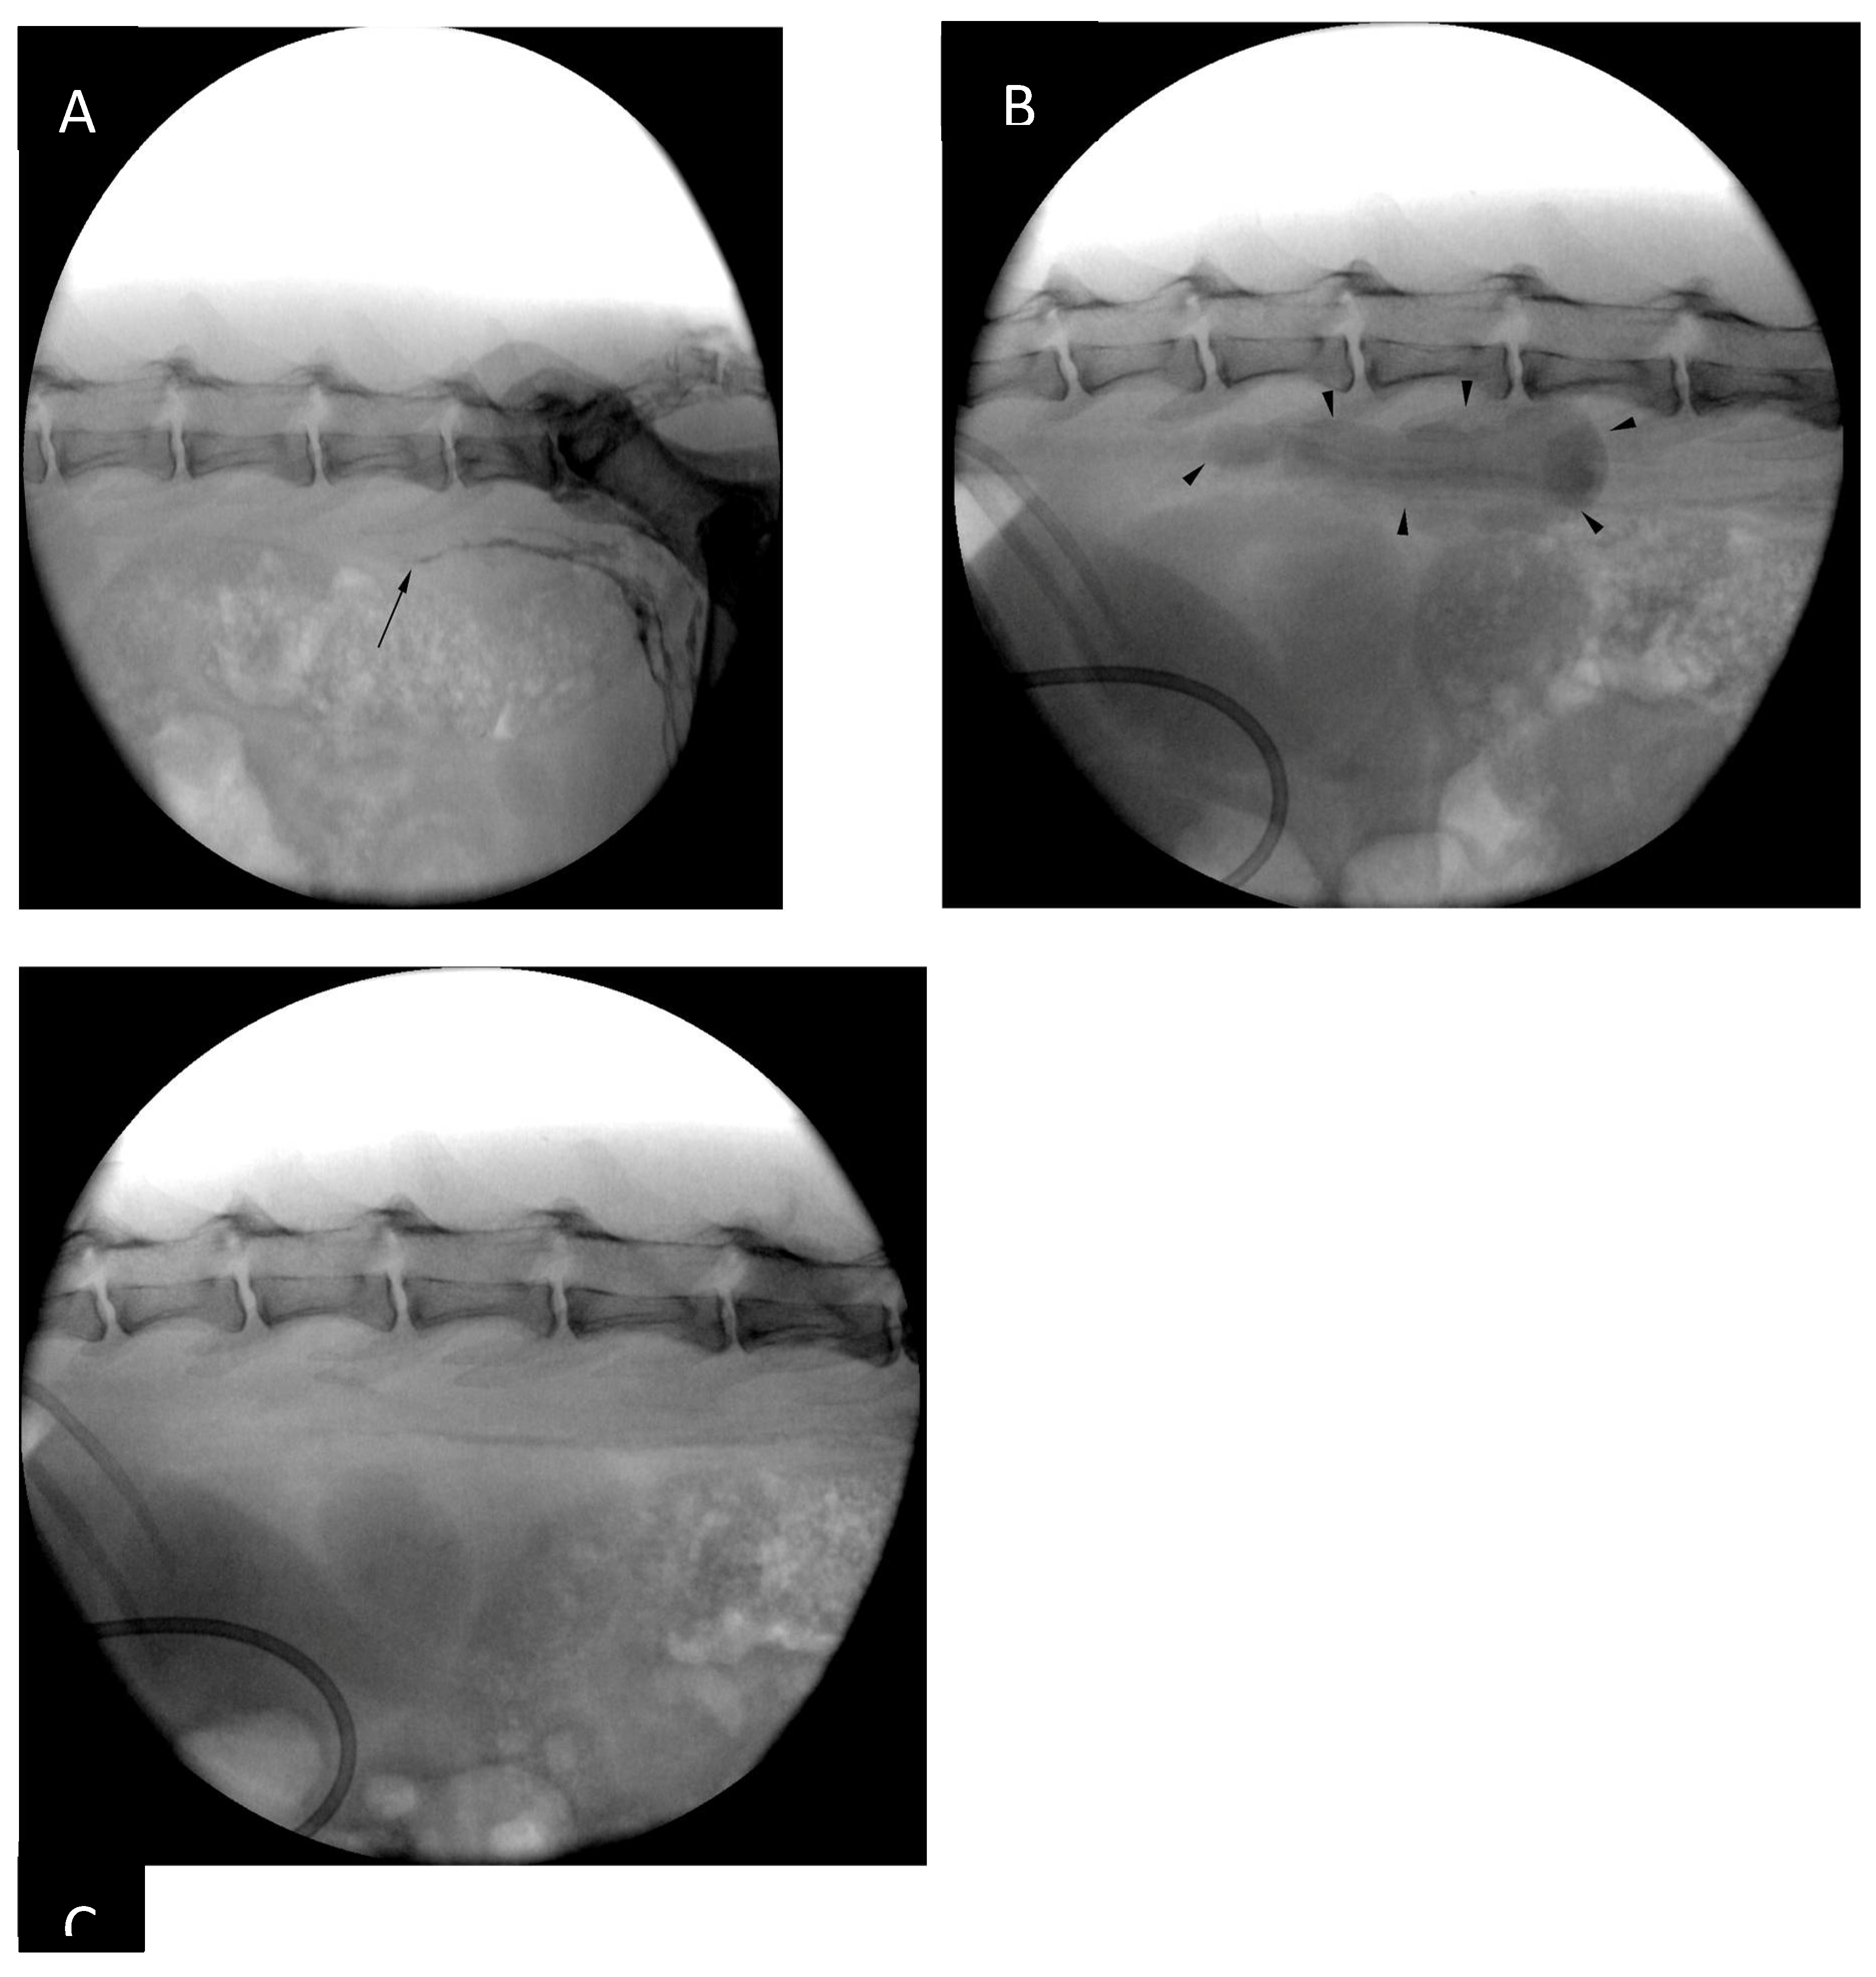

Figure 3. Fluoroscopy images obtained after bilateral intrametatarsal pad iohexol injection. (A) Opacification of the lymphatics is clearly visible up to the level of the caudal lumbar spine (black arrow) 2 minutes after the injection. (B) Opacification of the cisterna chyli (black arrowheads) can be seen at 14 minutes post-injection. (C) Fluoroscopy image taken immediately before ultrasound-guided access at 16 minutes post-injection (2 minutes after the image B had been taken). The opacification of the CC can no longer be appreciated.

The patient was placed in sternal recumbency for intrametatarsal pad injection of iohexol (Omnipaque 300 mg I / ml, GE Healthcare), 1.0 ml/kg divided in two sites (0.5 ml/kg/site), as described by Chiang et al. [14]. Following the injection and gentle massage of the pads the patient was positioned in left lateral recumbency and draped for right lateral sublumbar approach to the cisterna chyli (Figure 3). The contrast injection resulted in strong opacification of the lymphatics up to the level of the caudal lumbar vertebrae, however, the opacification was progressively less intense further cranially. By the time all the equipment was set up for CC puncture there was nearly no visible contrast within the CC (Figure 3).